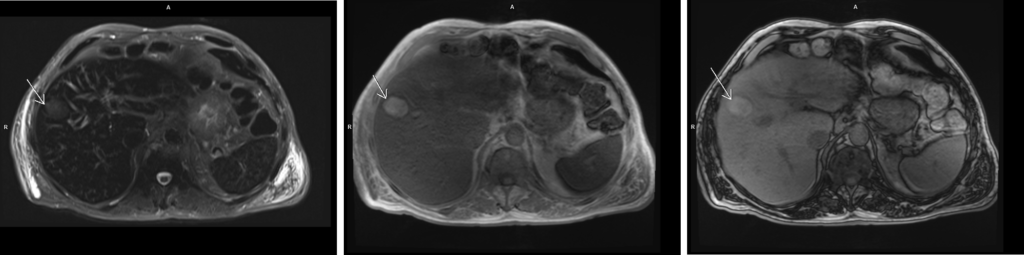

Figura 3: axial T2 FS, și T1 în și out-of-phase